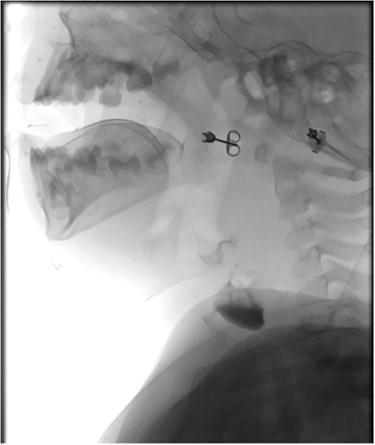

Sagittal barium sallow illustrating the presence of an oesophageal diverticulum, filled with contrast on swallowing.

At age 8 months, the patient was admitted to hospital from clinic due to worsening stridor. She underwent a further MLB that once again illustrated a cyst. An ultrasound scan was performed intraoperatively to aid with emptying of the cyst, and an incidental finding of a connection between the cyst and the cricopharyngeal region was identified, in keeping with a diagnosis of an oesophageal diverticulum. This was later confirmed on a barium swallow study (Fig. 4). Following the MLB, the patient remained clinically stable; the stridor resolved.